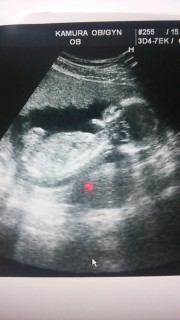

元気に成長してました!性別は、なんか付いてそうだけどまだ確定できないと言われました!笑 次回で確定します! たのしみ!!!

今日は戌の日と検診日。 旦那も一緒に。 赤ちゃんは順調みたいです。 性別はあっさりまだ分かんないよ~といわれガッカリ、、 次回まで持ち越しです。

頭3.7センチ☆窮屈そうに丸まってた(*^^*)

性別はわからず… もう可愛すぎ☆

最初は丸まってて頭からお尻までの大きさを正確にはかれませんでした(-_-;)頭の大きさは3.5センチくらいでした☆

CRLは11cmだったみたいです♪

成長の仕方、心拍が週数通りと言われ旦那と安心しました。 足をばたばた動かしていてとても可愛いかったです。 今回の写真では背骨がくっきり見えて成長を実感しました。